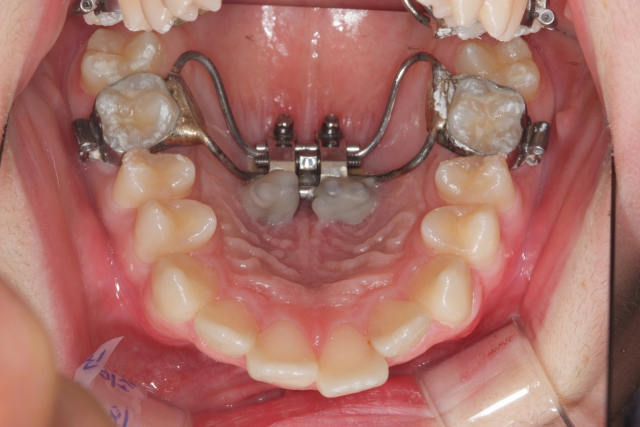

위 두 장은 MSE 시술 전후 입천장 모습. 위턱뼈가 벌어지면서 입천장이 확연히 넓어졌다. 이후 치아 배열을 하는 교정이 진행된다. 최종석치과의원 제공 위 두 장은 MSE 시술 전후 입천장 모습. 위턱뼈가 벌어지면서 입천장이 확연히 넓어졌다. 이후 치아 배열을 하는 교정이 진행된다. 최종석치과의원 제공